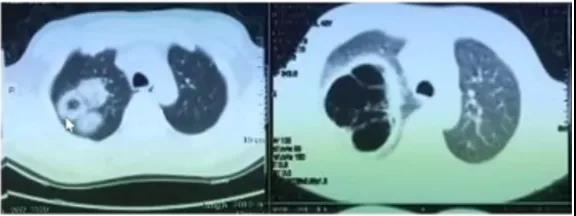

图5(左)患者是肾移植术后4个月,胸部CT可见磨玻璃影,提示肺孢子菌或CMV感染。下图(右)患者因呼吸困难就诊,胸部CT可见结节和磨玻璃影改变,患者有右心房增大,PET-CT提示恶性肿瘤可能性大,最终确诊为肿瘤所致弥漫性肺泡出血。

图5